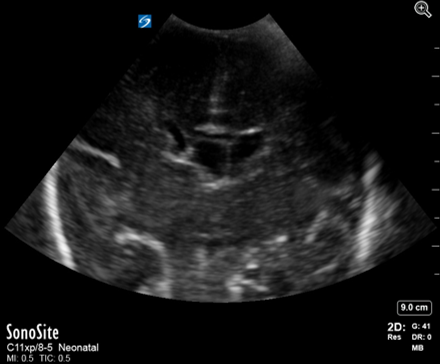

Neonatology Hydrocephalus Ex Vacu Image